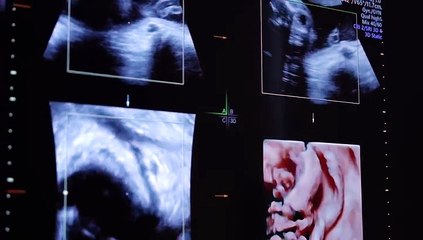

'Tüp bebek bile tutmaz' dediler çocuk sahibi oldularDİYARBAKIR - Çocuk sahibi olmak isteyen ama kendisinde polikistik over hastalığı, eşinde de sperm parametrelerindeki düşüklük nedeniyle tedavi gördükleri merkezlerde "tüp bebek bile tutmaz" denilen Fatma Dersan, Kadın Doğum ve Tüp Bebek Uzmanı Doç. br'Tüp bebek bile tutmaz' dediler çocuk sahibi oldularbrbrDİYARBAKIR - Çocuk sahibi olmak isteyen ama kendisinde polikistik over hastalığı, eşinde de sperm parametrelerindeki düşüklük nedeniyle tedavi gördükleri merkezlerde "tüp bebek bile tutmaz" denilen Fatma Dersan, Kadın Doğum ve Tüp Bebek Uzmanı Doç. Dr. Hakan Çoksüer'in uyguladığı ön tedavilerin ardından ilk tüp bebek denemesinde çocuk sahibi oldu. br Evliliklerini taçlandırarak çocuk sahibi olmak isteyen Diyarbakırlı Fatma ve Mahsum Dersan çifti, normal yollarla bebek sahibi olamayınca tedavi görmeye karar verdi.